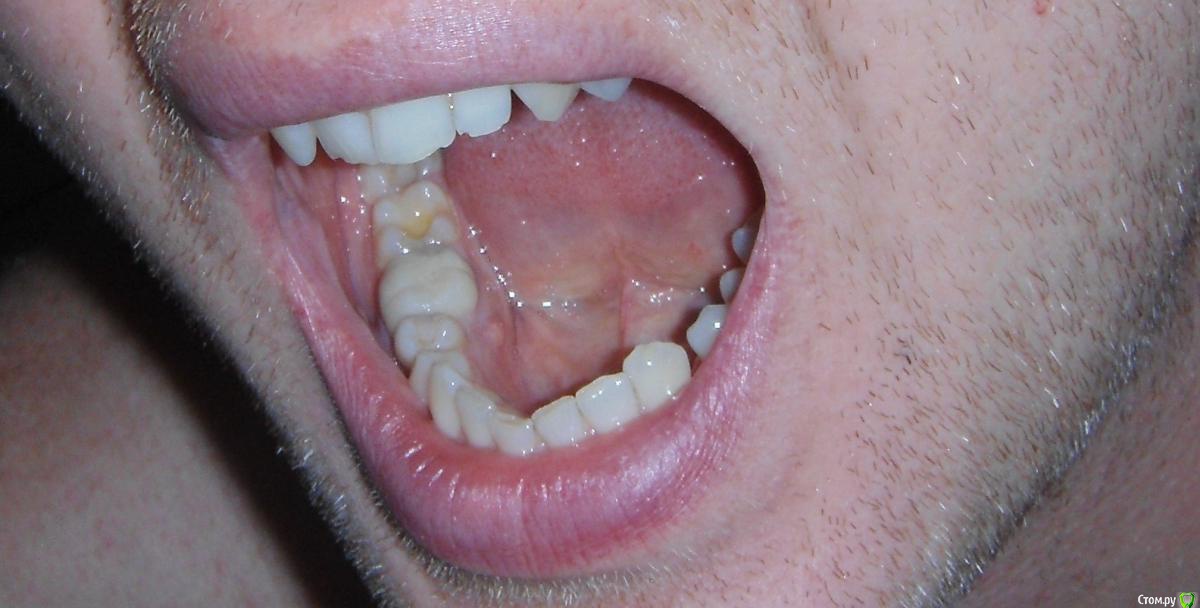

Капустин Роман Опубликовано 13 мая, 2018 Поделиться Опубликовано 13 мая, 2018 Добрый день! Нахожусь по работе в Никарануа г.Манагуа до декабря 2018 года. Стоит коронка с 2013 года. После чистки с внутренней стороны десны появился шарик. Врач предлагает удалить и поставить имплант. Хочется сохранить зуб. Насколько возможно? Спасибо. Ссылка на комментарий